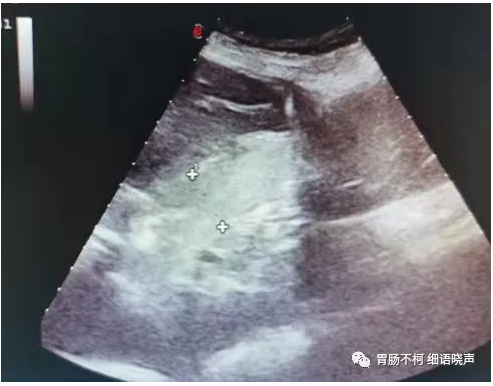

混合型:EGJ位于膈上,其旁可见部分胃移至膈上,两囊呈“双头征”。

病例三,混合型食管裂孔疝,膈上两囊呈“双头征”: